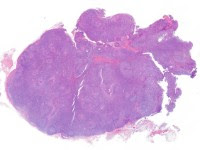

1. HE 2x

• Histológicamente se observa una tríada característica (también conocida como linfadenitis de Piringer-Kuchinka): un patrón de hiperplasia folicular con centros germinales reactivos, histiocitos epitelioides perifoliculares (ocasionalmente formando agregados en forma de microgranulomas e invadiendo los folículos) y una expansión paracortical de células B de aspecto monocitoide.